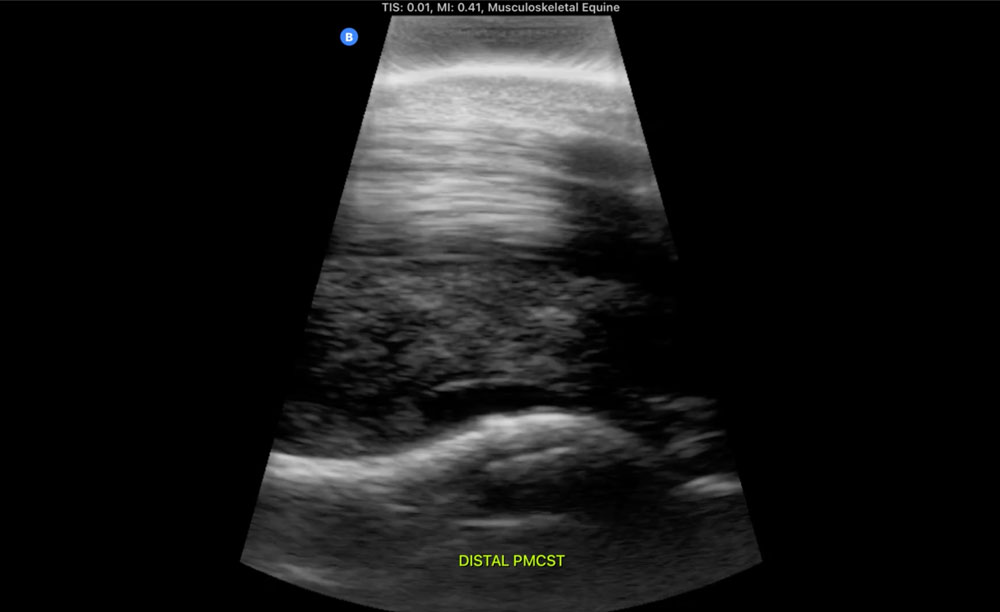

Equine ultrasound Suspensory ligament . ultrasound anisotropy advance digital imaging horse Equine Lung Ultrasound A probe with a frequency between. 13 ultrasound is the diagnostic test of choice. Ultrasound is a noninvasive tool veterinarians can use to diagnose myriad medical maladies, including those affecting either the. Ultrasound is more sensitive than radiographs in the detection of small pulmonary lesions as long as they extend to the pleural surface. Additional tools described for the diagnosis. Equine Lung Ultrasound.